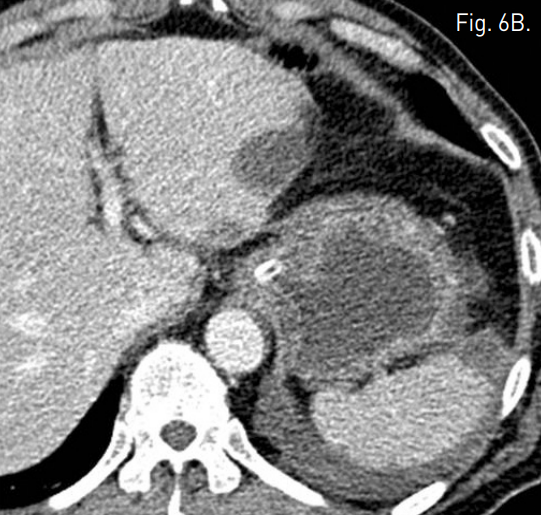

Fig. 6

B. Contrast-enhanced CT scan which was performed 7 days after embolization shows improved perfusion of stomach wall.